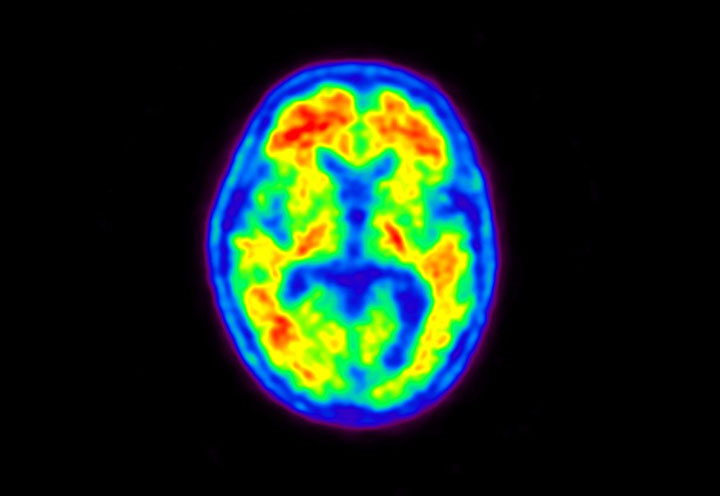

Head / Case5 : Amyloid

Courtesy : Kindai University Hospital

- Imaging protocol

- Injected dose: 4.27 MBq/kg, 18F-Flutemetamol

- Uptake time: 99 minutes

- Scan time: 20 minutes